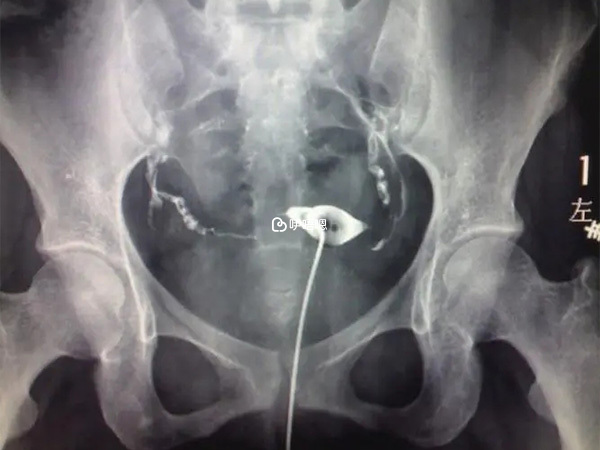

14年4月做的造影,本來對結果我都不抱什麼希望了,造影結果卻還不錯,雖然不是通的,但起碼沒有堵啊。帶著糾結的心去找了我的主治醫生,醫生看了說,不錯,比預期的好太多,接著就開了三個月的灌腸藥,加上達英和調理多囊的中藥。